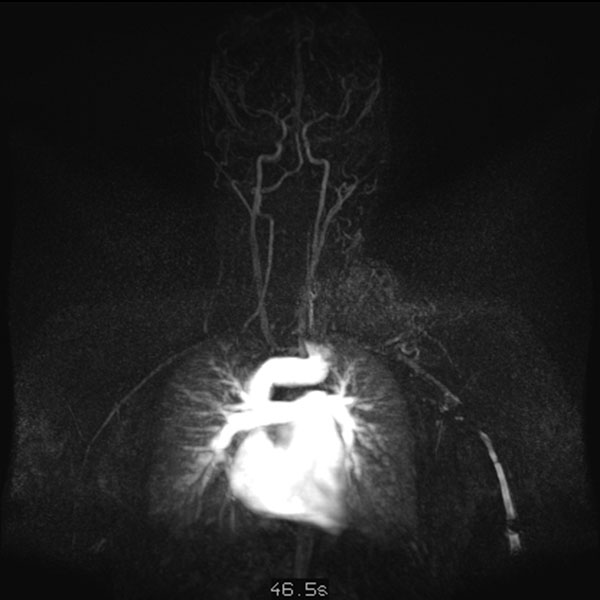

Dynamische, kontrastmittelunterstützte, zeitlich hochaufgelöste MR-Angiographie; Darstellung 57 s nach intravenöser Kontrastmittelapplikation. Weitere 5 s später nochmals bessere Darstellung des venösen Abstroms aus der arteriovenösen Malformation.